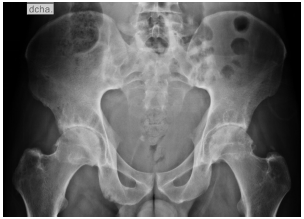

Due to inflammatory back pain, pelvic X-rays were requested, with evidence of bilateral grade III sacroiliitis (Fig. 1).

Fig. 1 Anteroposterior projection of the pelvis showing changes of enthesopathy and bilateral grade III sacroiliitis, confirming the diagnosis of ankylosing spondylitis.